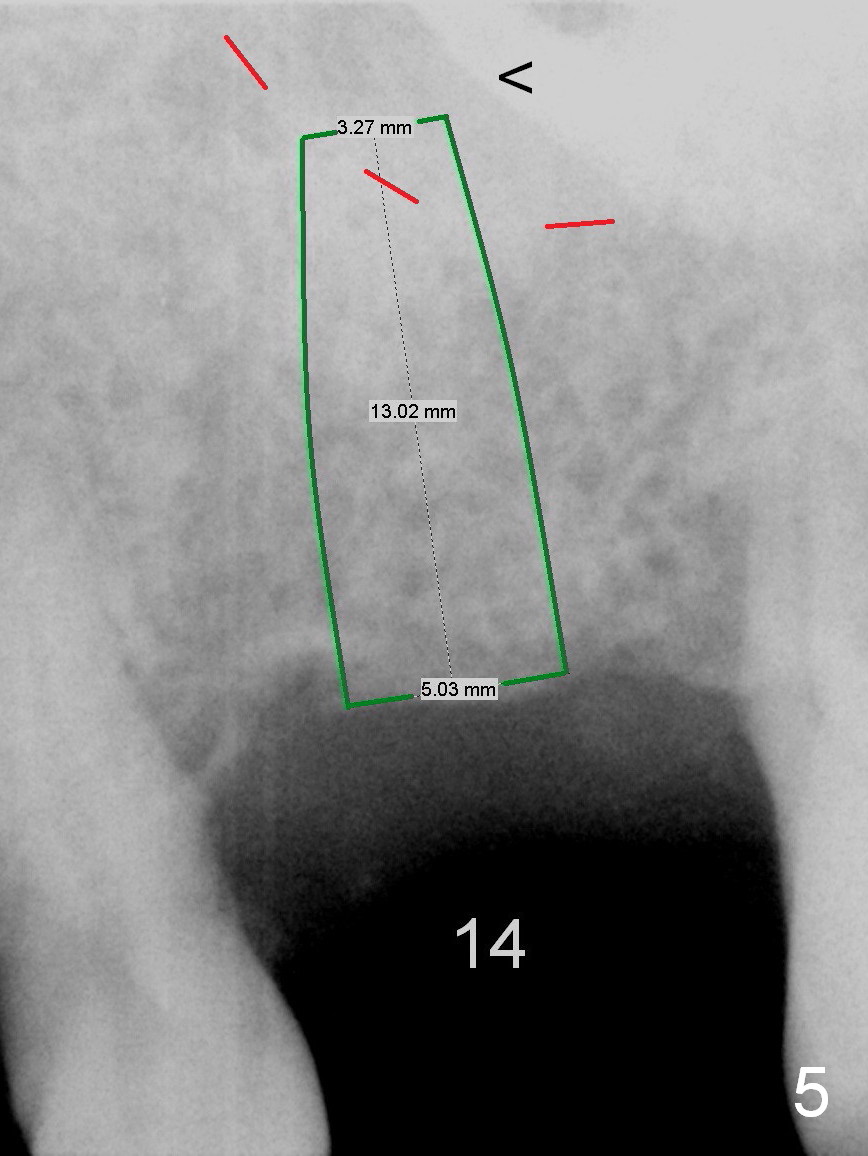

Re-analysis of #14 edentulous area reveals slightly unfavorable crown/implant ratio if the implant reaches the 1st line of the sinus floor (Fig.4). A 5x13 mm implant may invade the 1st line (Fig.5). Therefore the depth of osteotomy using 4.8 mm Magic Drill is 9-10 mm (Fig.6 green), followed by Magic Sinus Lifter, unless the bone density is high.